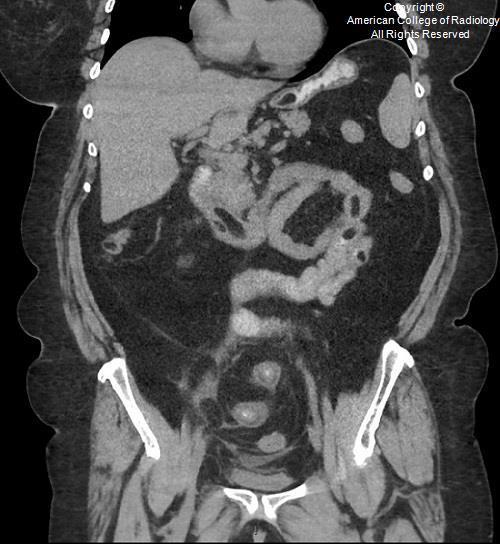

Vesicoureteral Reflux Grading

Most low-grade VUR resolves sponta- neously by the age of 5 to 6 years unless there is an underlying anatomic abnormality.

Figure example:

Right side - Grade 2

Left side - Grade 5